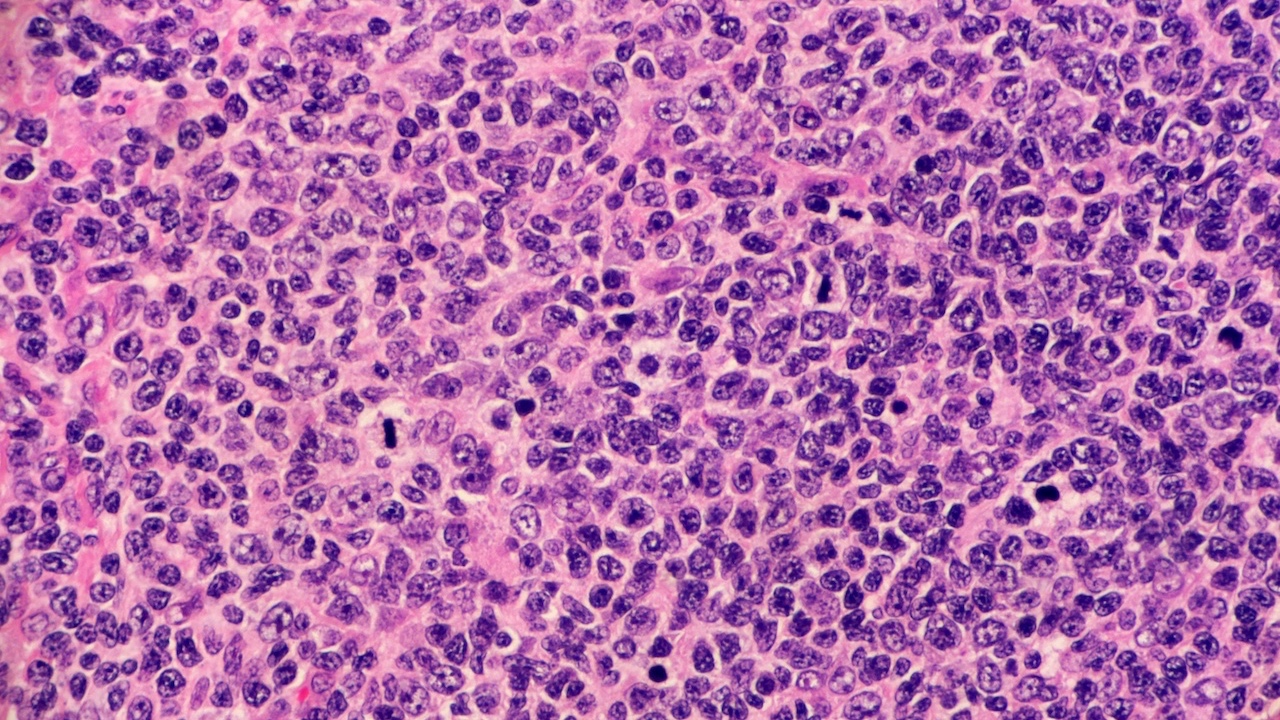

Revised MALT-IPI: A New Predictive Model that Identifies High-risk Patients with Extranodal Marginal Zone Lymphoma October 6, 2022